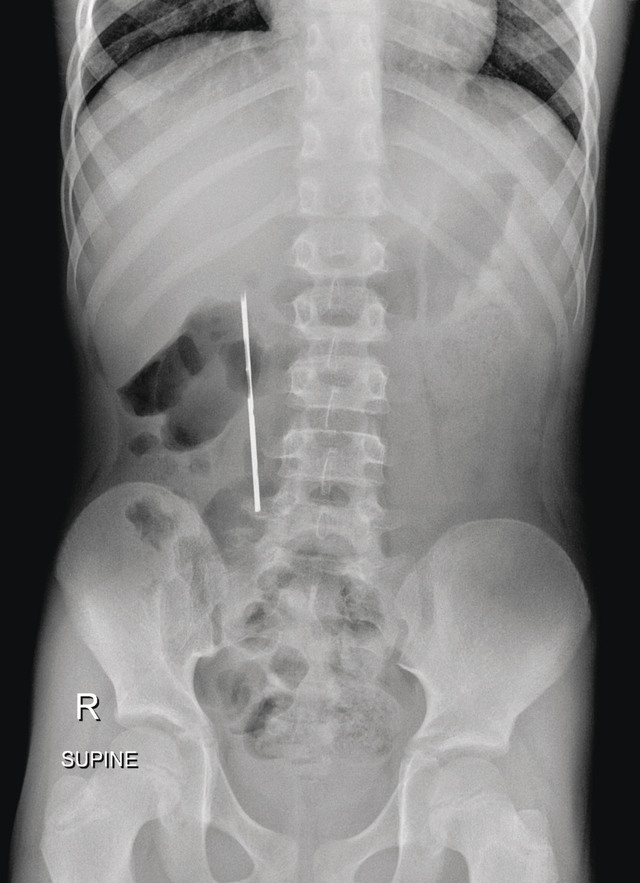

وصل الطفل إلى المستشفى وهو يعاني من آلام حادة في البطن، وبعد إجراء الفحوصات والأشعة اللازمة، اكتشف الأطباء وجود أجسام معدنية في معدته، مما استدعى تدخلاً طبيًا عاجلًا.

بعد التأكد من حالة الطفل، قرر الأطباء التدخل باستخدام المنظار الهضمي العلوي لتجنب أي مضاعفات خطيرة قد تنتج عن بقاء هذه الأجسام المعدنية في المعدة.

تمت العملية بنجاح، وتم استخراج جميع القطع المعدنية التي تضمنت عملات معدنية وأشياء صغيرة أخرى، والتي يُرجح أن الطفل قد ابتلعها عن طريق الخطأ أو بدافع الفضول.